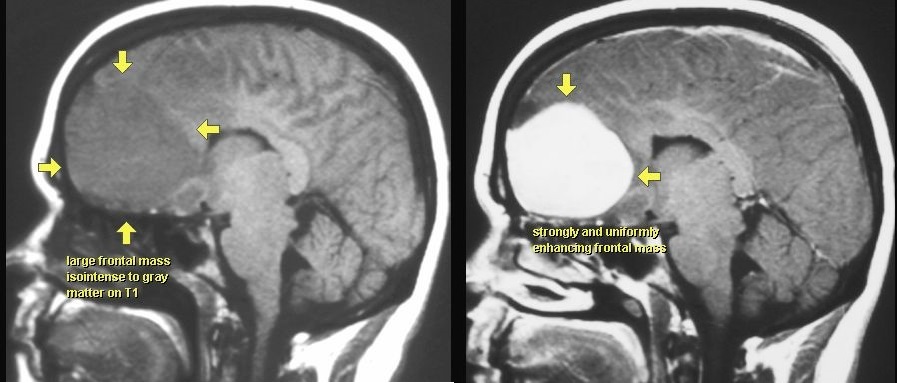

OPONIAK

MRI